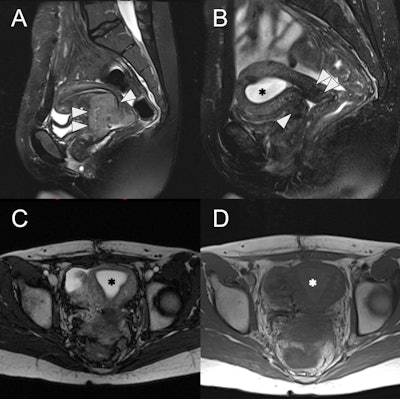

24-year-old female with radiation-induced cervical stenosis. (A) Pretreatment sagittal fat-suppressed T2w MRI of the uterus with a large intermediate to high signal intensity cervical mass (white arrowheads), FIGO stage IIB. (B) Sagittal fat-suppressed T2w MRI postchemoradiation showing marked regression of the tumor (white arrowheads) with reconstitution of the low signal intensity cervical stroma and no measurable residual mass. However, there is new distention of the endometrial cavity (asterisk) with high signal intensity. (C) Axial T2w MRI of the uterus with a distended endometrial cavity (asterisk), suggestive of obstruction. (D) Axial T1w MRI of the uterus shows mild hyperintensity (asterisk) of the endometrial fluid compared to myometrium, suggestive of hematometra